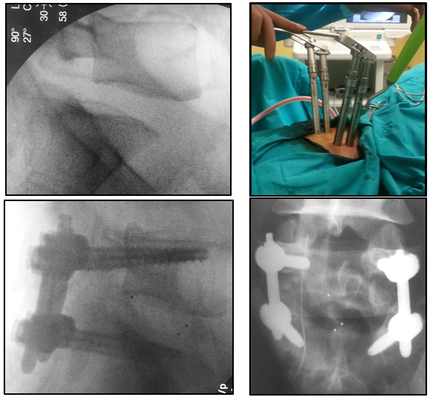

Для ещё одной иллюстрации малой травматичности перкутанной ТПФ приведём публикацию, в которой авторы описывают возможность проведения операции в условиях локальной анестезии у соматически отягощённых пациентов (рис.6) [10].

Рис. 6